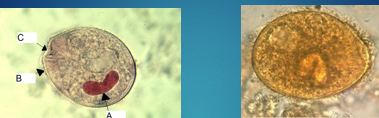

P. Vivax schizont

B. Coli

B. Coli Cysts